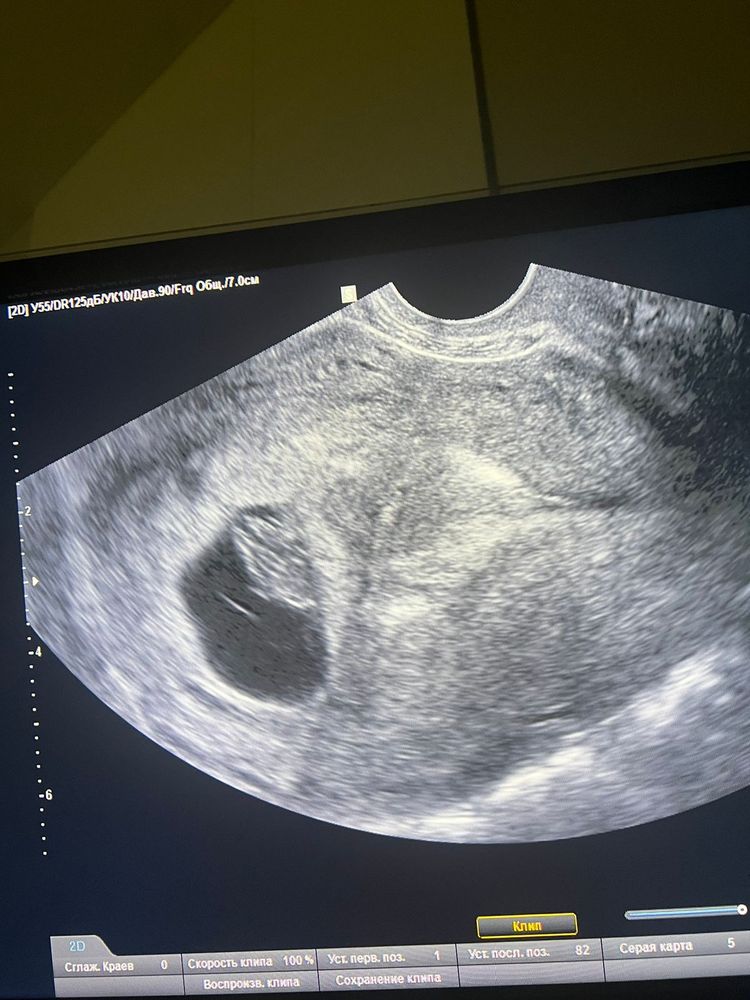

8 недель, узи. Наши результаты.

была уже 2 раза на узи, 1й раз в 6 недель , там нашли пульсацию, и пузырик подтвердили беременность, потом в жк сказали сходить еще на одно чтобы уже было сердцебиение , вчера вечером была на узи, такая 🥰 прелесть.

Ктр плода 17 мм, соотв 8 Нед

чсс 156

жм 4 мм

жт 20 мм